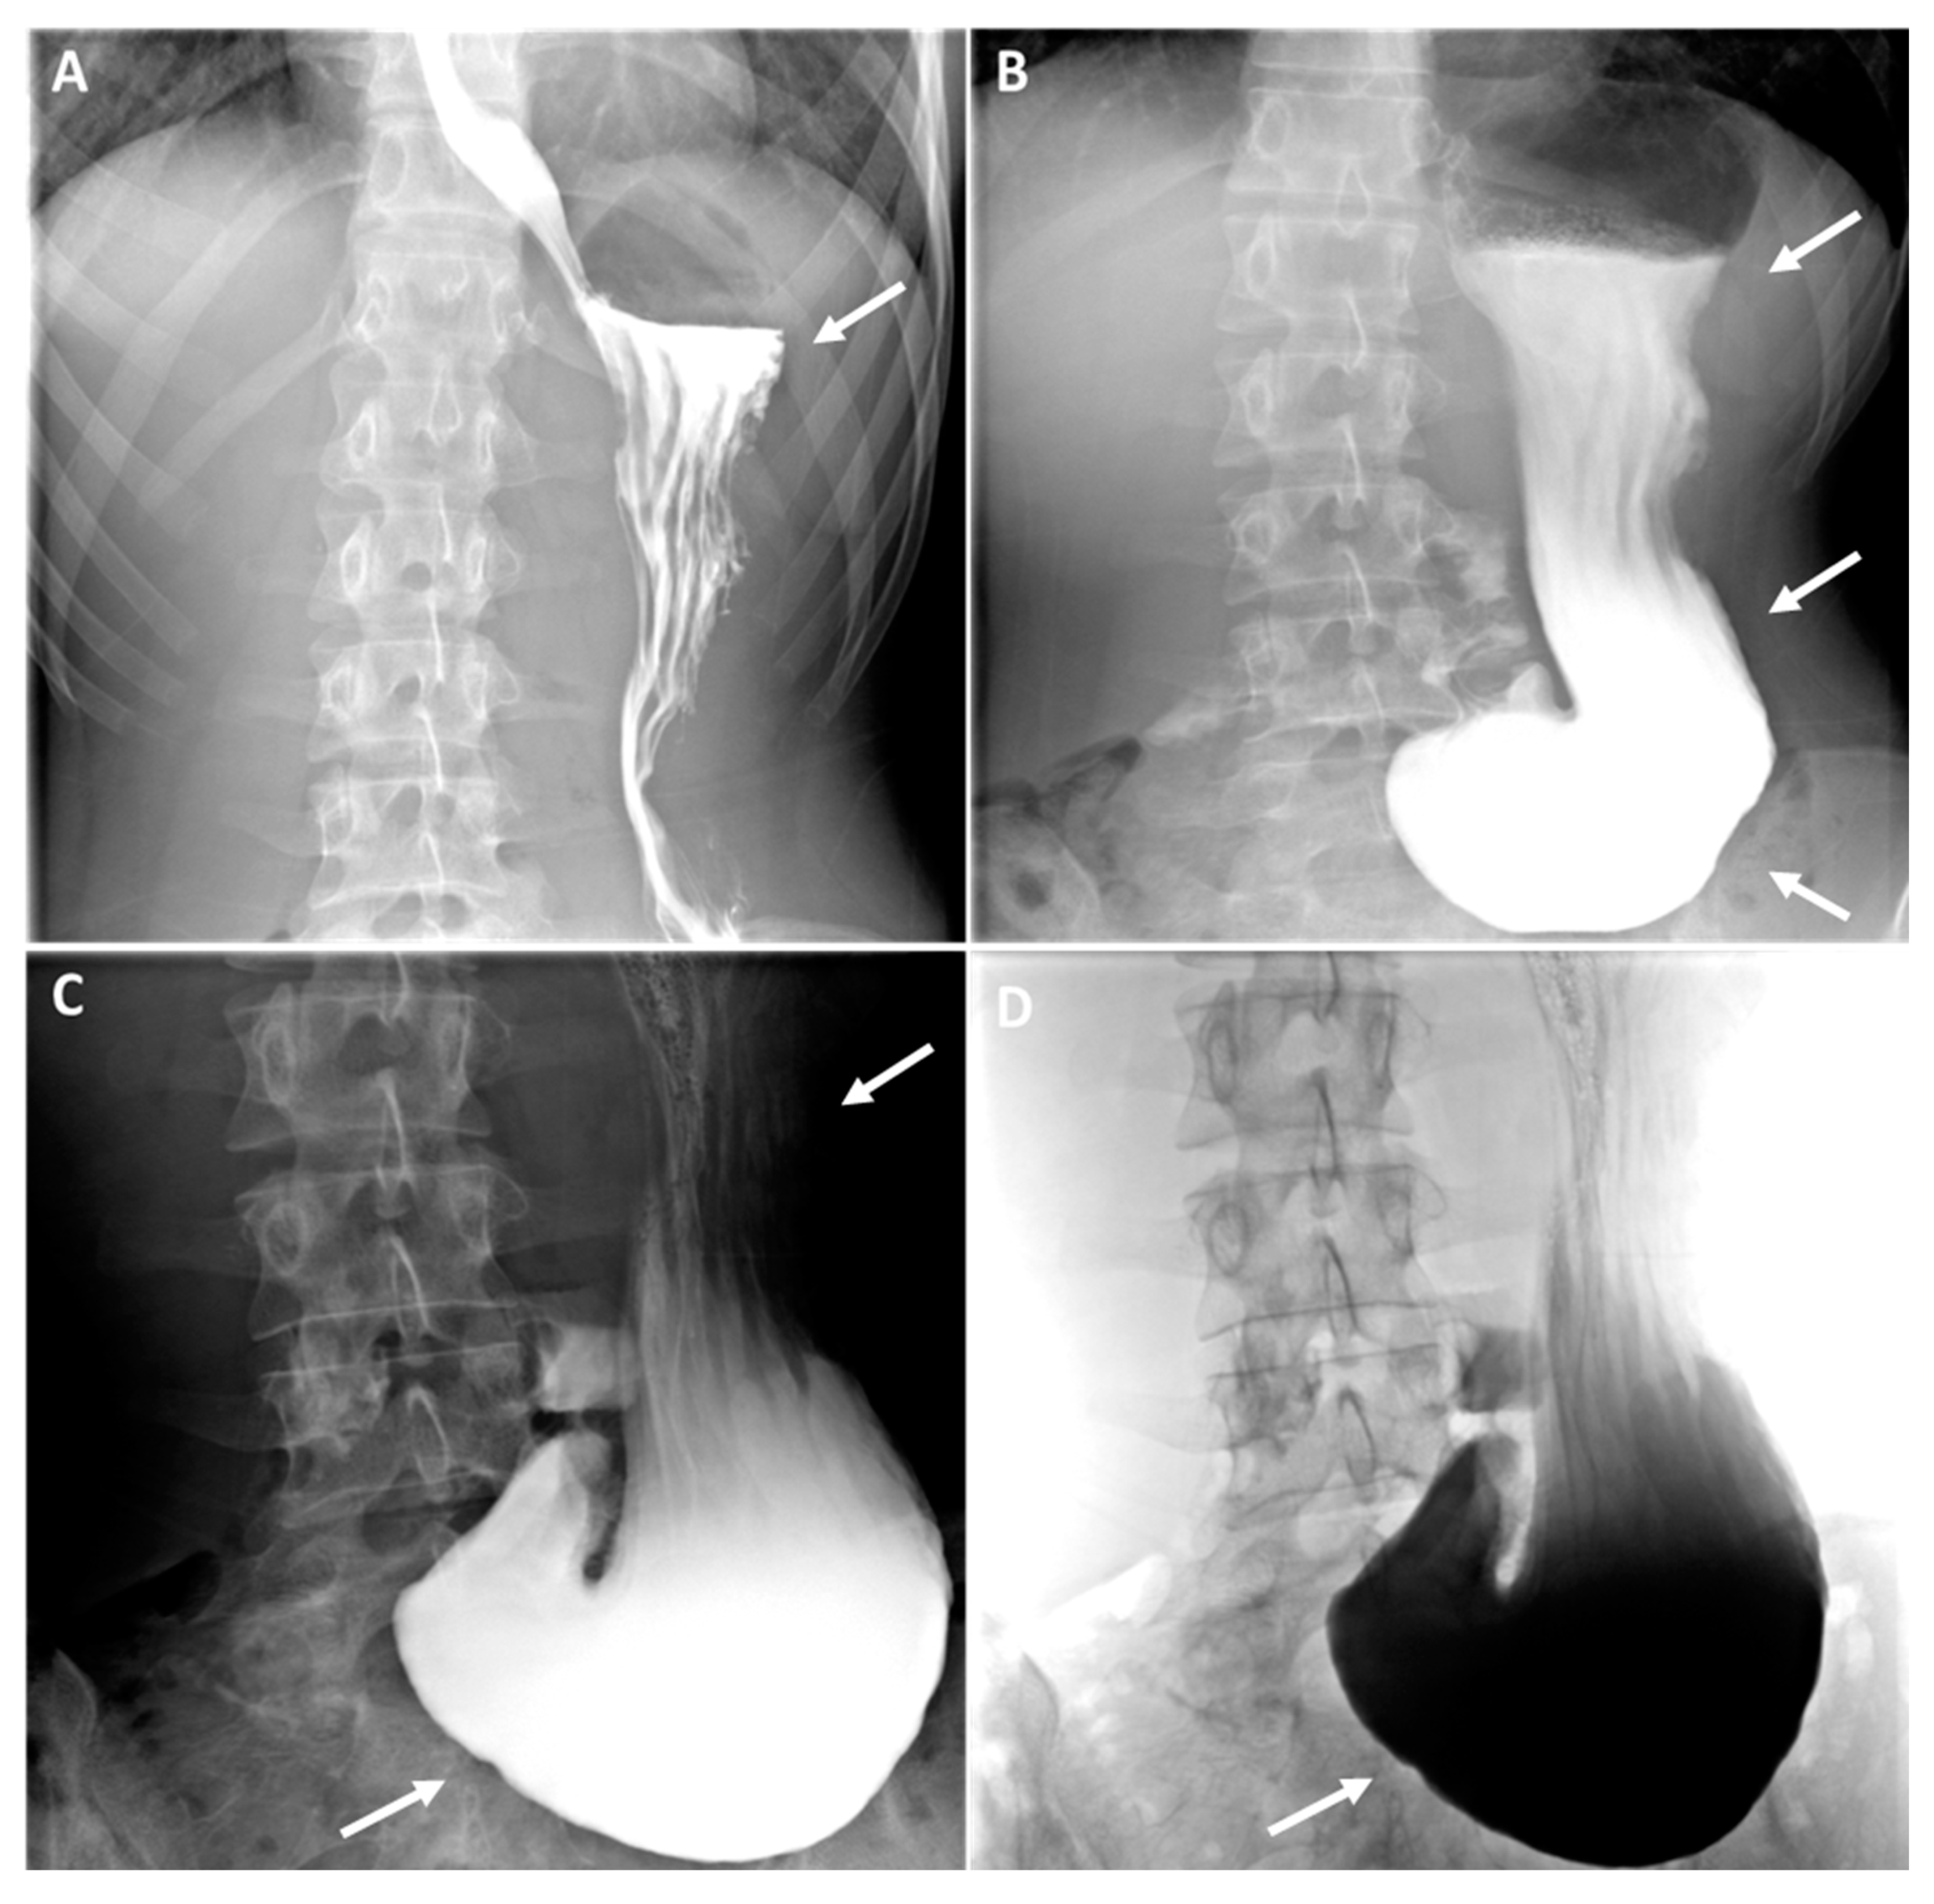

As evidenced by the existing literature, imaging has a crucial role in the diagnostic process of gastroptosis and SMAS [19]. Fluoroscopy with oral barium or iodine contrast remains the primary assessment tool of the upper gastrointestinal tract, offering real-time dynamic visualisation that facilitates the correlation of clinical history with imaging [4,19,20]. In both case, fluoroscopic findings generally include gastrointestinal distention (Figure 2, white arrows where the stomach is displaced downwards, with the greatest curvature close to the iliac crest, while the antrum remains in place), delayed gastric emptying (Figure 2, dynamic A-D) and narrowing of the third part of the duodenum (less obvious in our case). Further information can be obtained by computed tomography (CT), which, in combination with intravascular contrast, allows detailed assessment of the aorto-mesenteric vascularisation and calibre of the gastroduodenal structures, proving invaluable in the diagnosis. SMAS syndrome is characterised by gastroduodenal dilatation with marked narrowing at the junction of the AMA and the aorta (Figure 1, red arrow), shortening of the aorto-mesenteric distance (normal: 10-34mm; 1B), and tightening of the aorto-mesenteric angle (normal: 28-65°; Figure 1C) [19,20,21]. Gastroptosis may also be visible, depending on whether or not the patient has eaten prior to the examination; however, it may be less visible if the examination is performed on an empty stomach.

Figure 1. We present the case of a 17-year-old girl who presented to her general practitioner and the gastroenterology department with her parents because of epigastric pain, nausea, vomiting and significant progressive weight loss (11kg in 6 months). The patient reported a feeling of heaviness and abdominal discomfort, especially after meals, accompanied by nausea and vomiting, which had been progressive over the last few months. She explained that her appetite had remained relatively stable and that she continued to eat relatively well and healthily without changing her diet. However, she was concerned that continuing to eat would lead to a worsening of her symptoms. She had visited the emergency department several times with her symptoms and had tried various pharmacological agents, including proton pump inhibitors (PPIs) and antispasmodics, in an attempt to alleviate her condition. However, these interventions provided only minimal symptomatic improvement. The rest of her medical history was unremarkable, with no history of fever, dysphagia (solid or liquid), transit disorders, constipation or diarrhea, chest pain or dyspnea. His medical and surgical history was devoid of any noteworthy abnormalities. The family history was unremarkable. The infant was delivered via spontaneous vaginal delivery at 38 weeks of gestation with a birth weight of 2750 grams. The infant was breastfed until the age of 1.5 months, exhibited normal growth and development, and is up to date with her vaccinations. The patient's clinical parameters at the time of consultation were found to be entirely satisfactory, with the following observations: blood pressure of 120/64 mmHg, heart rate of 74 bpm, body temperature of 36.1°C, and an oxygen saturation of 100% on room air. The subject's weight was 45 kg for a height of 164 cm, resulting in a body mass index of 16.7 kg/m². On clinical examination, cardiopulmonary auscultation was within normal limits, and abdominal examination revealed epigastric tenderness radiating to the umbilicus, but no associated mass or rebound. Peristalsis of the digestive tract was noted to be intact. Given the circumstances, additional diagnostic procedures were initiated. Laboratory investigations revealed no haemogram abnormalities, no acute and/or chronic inflammation (C-reactive protein (CRP) and erythrocyte sedimentation rate (ESR) negative), preserved renal function, a satisfactory ionogram, normal thyroid function (TSH and fT4 N) and normal phospho-calcium balance (PTH and 25-OHD normal). A test for celiac disease was negative (total IgA and anti-transglutaminase antibodies normal). Faecal calprotectin (FC) levels were also normal (<100 µg/g, N <100 µg/g), ruling out inflammatory bowel disease (IBD). An endoscopic examination of the stomach revealed erythematous gastritis, with no additional microscopic abnormalities identified. An abdominal computer tomography scan (CT-scan) with injection of contrast medium demonstrated a duodenal stricture over a mesenteric pinch (Figure 1, red arrow). Furthermore, a barium radiographic examination was carried out and shown severe elongation of the stomach down to the umbilicus, suggestive of gastroptosis (Figure 2, white arrows). The patient was diagnosed with gastroptosis associated with superior mesenteric artery syndrome.